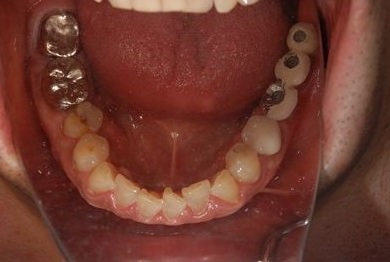

| 性別/年齢 | 男性 / 69歳 | ||||||||||||||||||||||||||||||||

| 主訴 | 1.左上奥歯の詰め物が取れた 2.左上前歯の欠け 3.右下奥歯の欠け | ||||||||||||||||||||||||||||||||

| 治療方針 | セラミック治療にて、審美的回復を行う。 | ||||||||||||||||||||||||||||||||

| 治療内容 | メタルボンドセラミッククラウン1本(メタルボンド用土台1本)、ハイブリッドセラミックインレー1本 | ||||||||||||||||||||||||||||||||

| 総治療費 | 172,410円 | ||||||||||||||||||||||||||||||||

| 治療期間 | 4ヶ月 |